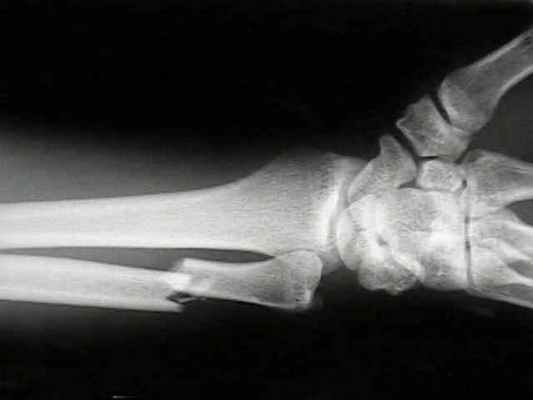

Остеосинтез при переломах дистального отдела лучевой кости производят редко, как правило, при неудаче консервативного лечения. Для остеосинтеза применяют малую Т-образную пластину (Рис. 140).

Первый винт вводят через продолговатое отверстие в проксимальный отломок, тем самым создавая опору для дистального фрагмента. Сам отломок фиксируют компрессионным спонгиозным винтом через отверстие пластины. Рану ушивают с тщательным восстановлением квадратного пронатора. Движения в лучезапястном суставе разрешают через 3–5 дней.

В некоторых случаях остеосинтез производят спицами или спонгиозным винтом.

Остеосинтез лучевой кости в дистальном отделе